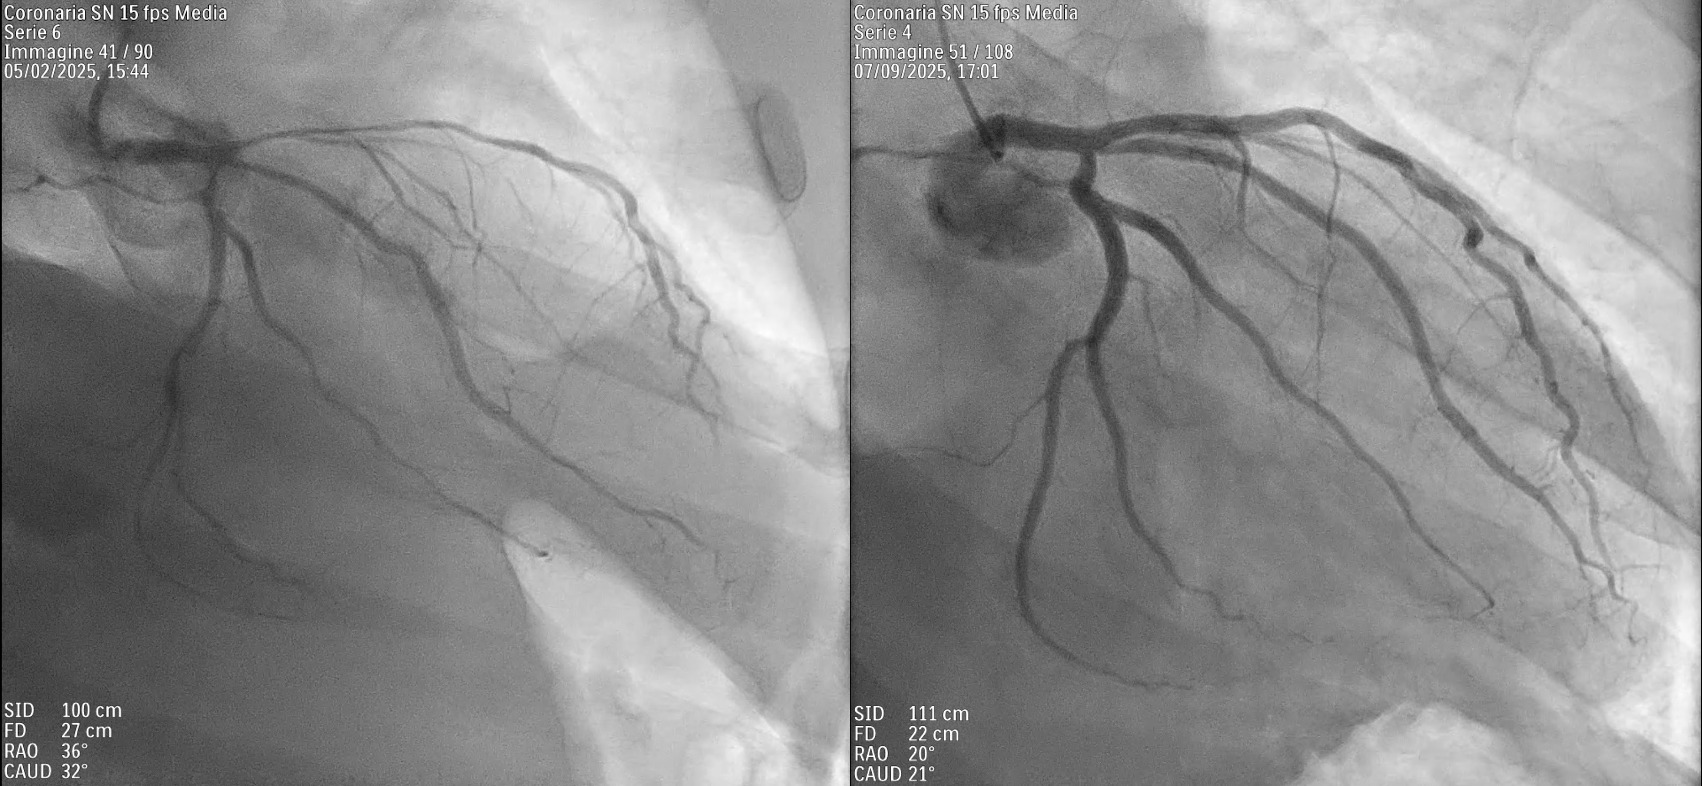

Background Primary cardiac lymphoma is an extremely rare condition, accounting for less than 0.5% of extranodal lymphomas. It can present with a variety of symptoms, including pericardial effusion, heart failure, arrhythmias, or coronary artery compression. Accurate diagnosis requires a multimodal imaging approach—utilizing echocardiography, cardiac magnetic resonance (CMR), and PET-CT—complemented by cytological or histological confirmation. Case Description A 62-year-old male with a history of B-cell lymphoma presented to the Emergency Department with pleuritic chest pain and pericardial and pleural effusions. Despite initial treatment for suspected pericarditis with colchicine and ibuprofen, the patient’s condition progressed to hemodynamic compromise, requiring pericardiocentesis. Cytologic analysis and a supraclavicular mass biopsy confirmed recurrence of high-grade B-cell non-Hodgkin lymphoma. PET-CT imaging showed systemic spread with significant cardiac and pleural uptake. During hospitalization, the patient developed hypoxemia, hypotension, and acute chest pain. CT angiography excluded embolism but identified extrinsic compression of the right pulmonary artery. Concurrently, ECG changes and new regional wall motion abnormalities (posterolateral hypokinesia) appeared, with a decline in left ventricular ejection fraction (LVEF). Coronary angiography demonstrated critical stenoses of the left anterior descending, intermediate, and circumflex arteries, all suggestive of extrinsic compression. CMR further confirmed extensive intramyocardial infiltration. Following the failure of first-line Polatuzumab-Rituximab, second-line therapy with Obinutuzumab and Glofitamab was initiated. This targeted approach led to progressive lesion regression, normalization of ventricular function (LVEF improved from 38% to 56%), and complete resolution of the coronary stenoses. Conclusions This case highlights the importance of considering cardiac lymphoma in the differential diagnosis of recurrent pericardial effusion, unexplained ventricular dysfunction, or atypical coronary stenoses, particularly in patients with a history of lymphoproliferative disease. Integrating advanced imaging with histological confirmation is essential for diagnosis and targeted immunochemotherapy. These therapies can effectively induce mass regression and complete functional cardiac recovery, including the resolution of extrinsic vascular compression.